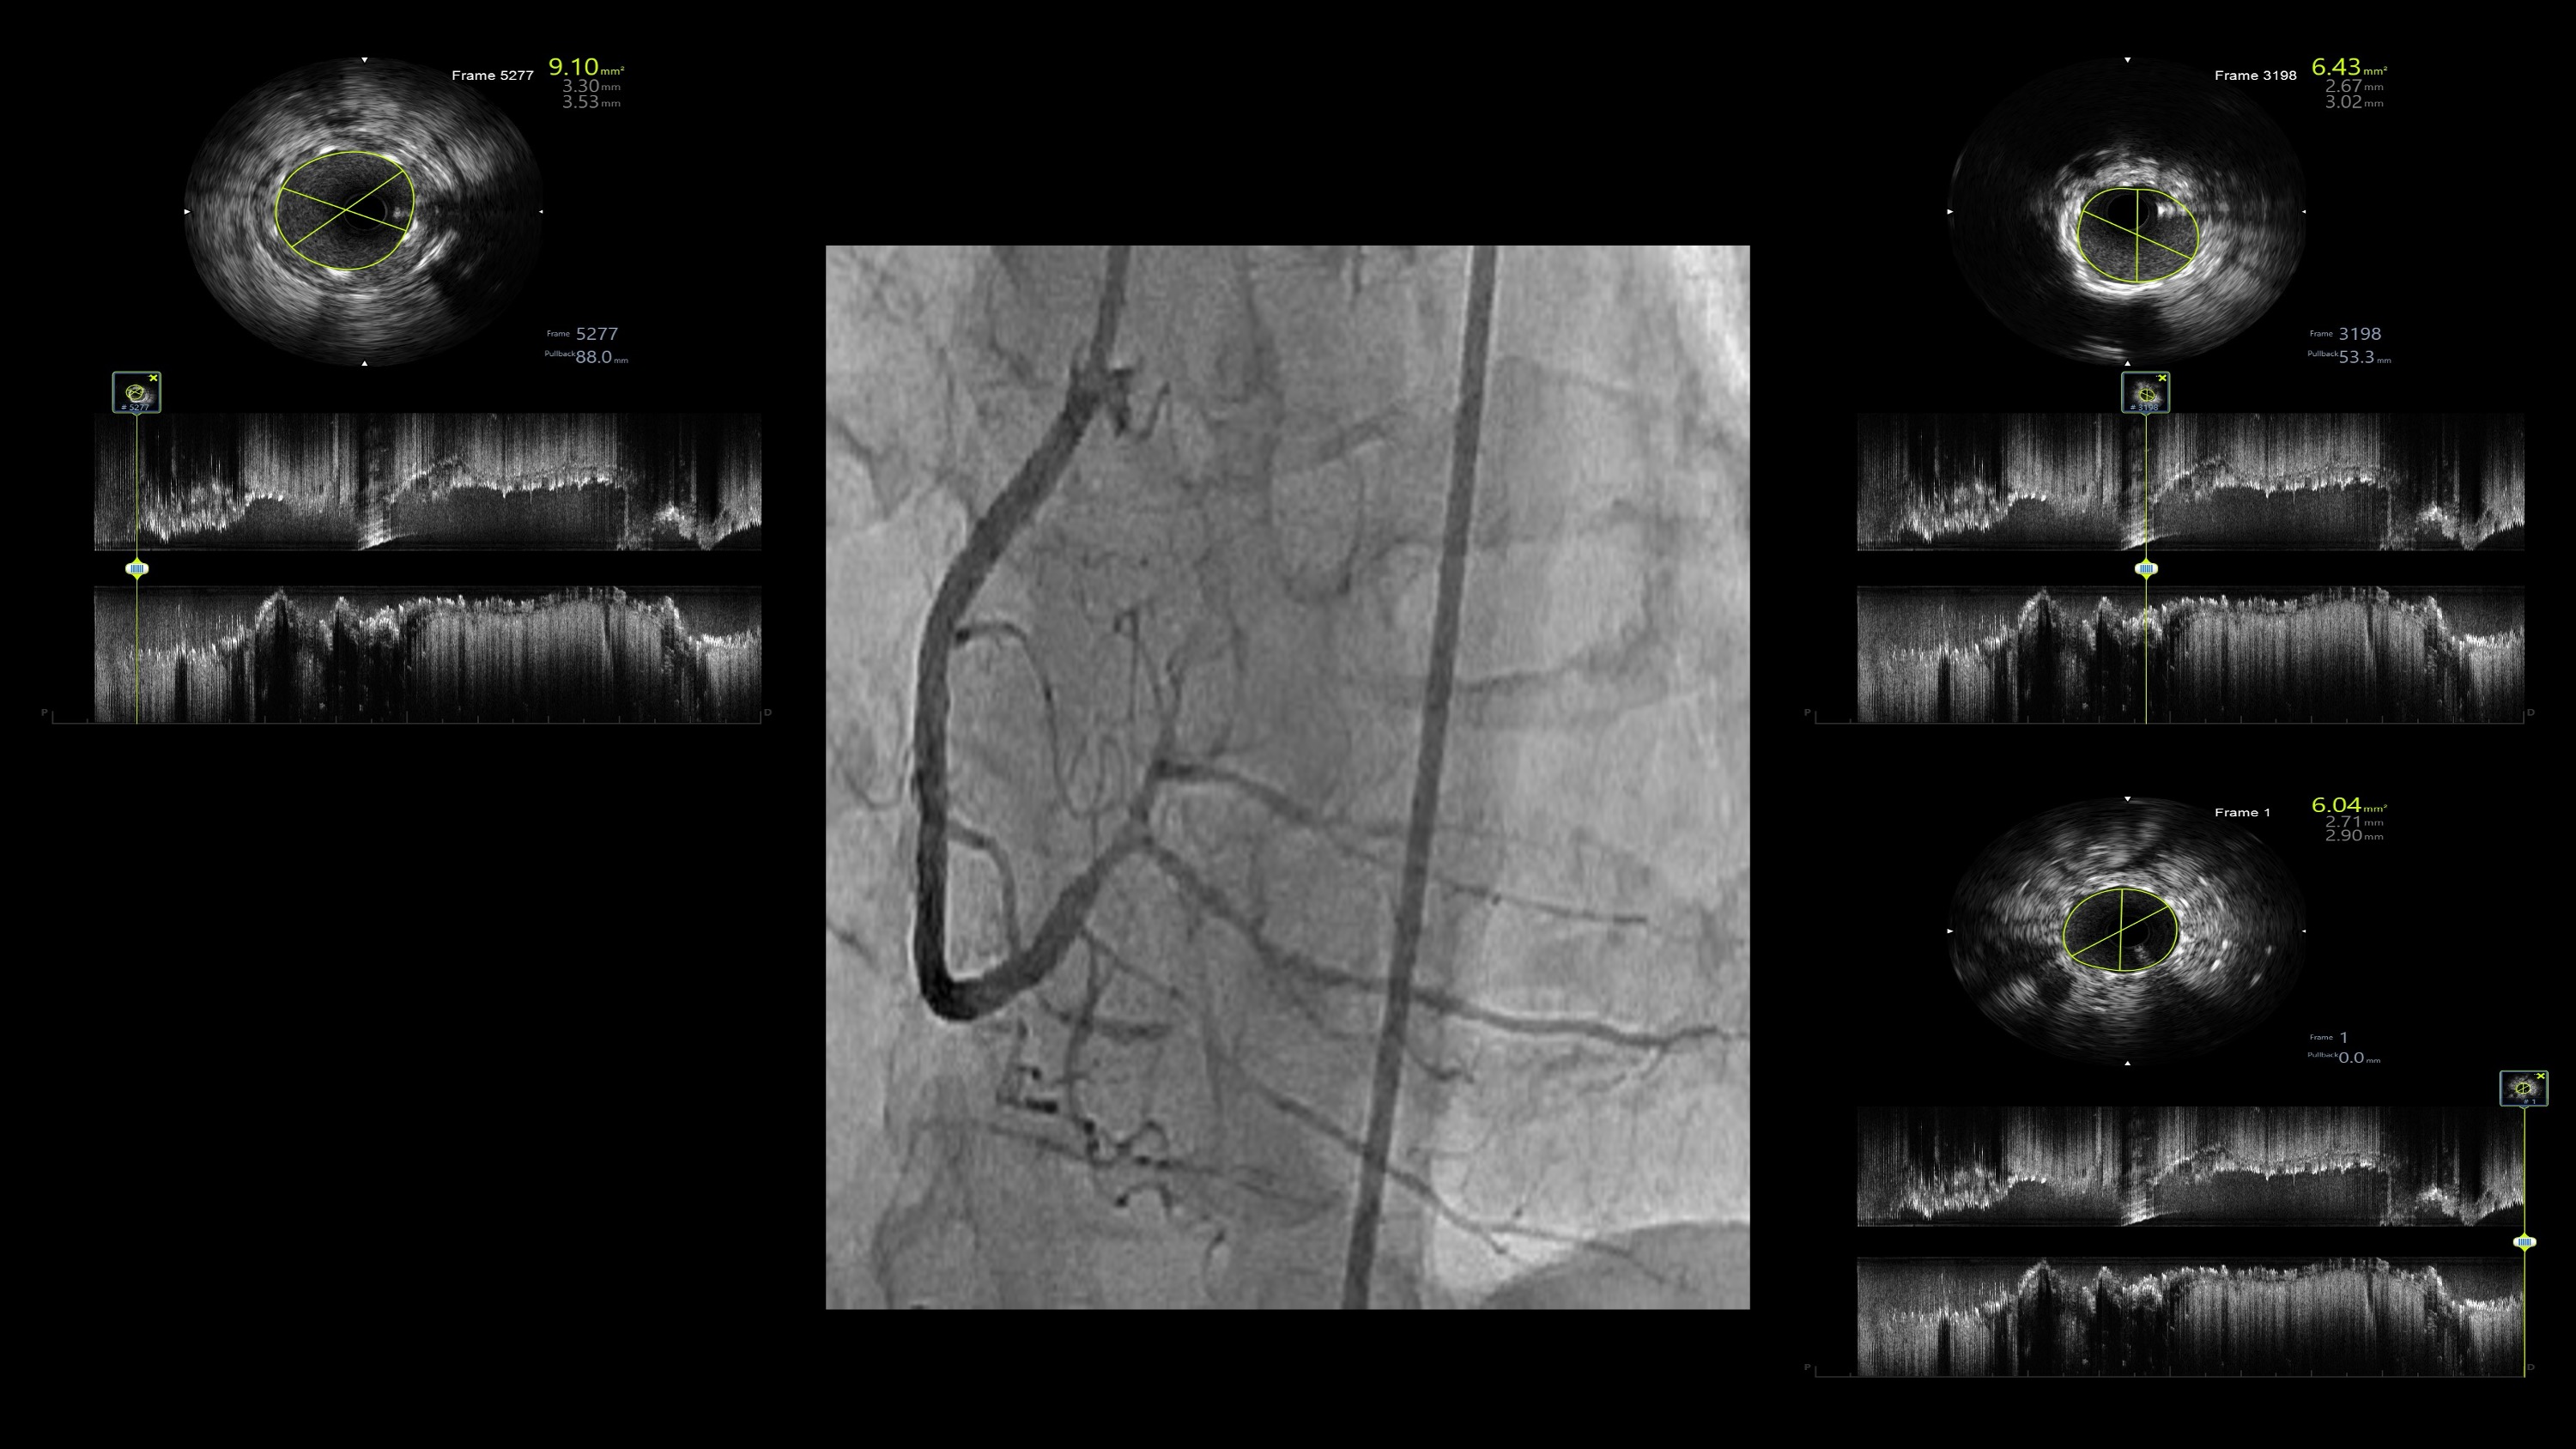

When even the smallest CTO balloon failed to cross, the burr became the breakthrough. Rotational atherectomy transformed an unyielding, calcified RCA into a successfully revascularized vessel. Guided by IVUS and supported by meticulous technique, the procedure achieved excellent stent expansion, optimal apposition, and restored TIMI III flow — reaffirming that in complex, calcified coronary lesions, Rota ablation remains the key when nothing else can pass